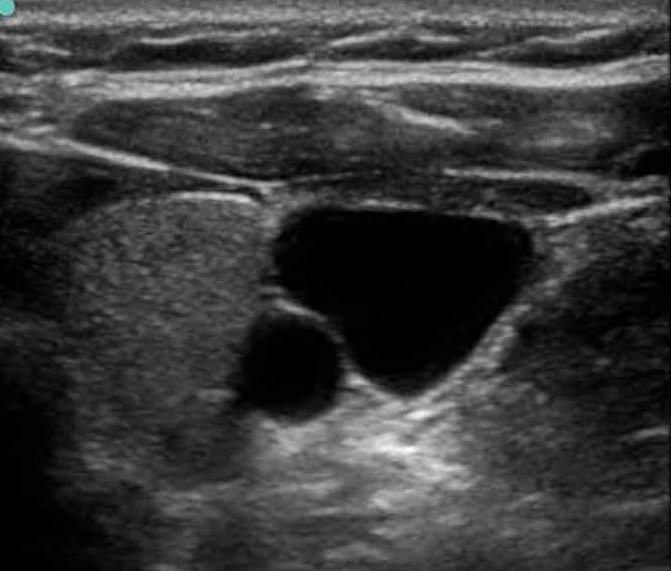

血管通路 1 图像

M-Turbo:IJV 短轴 1